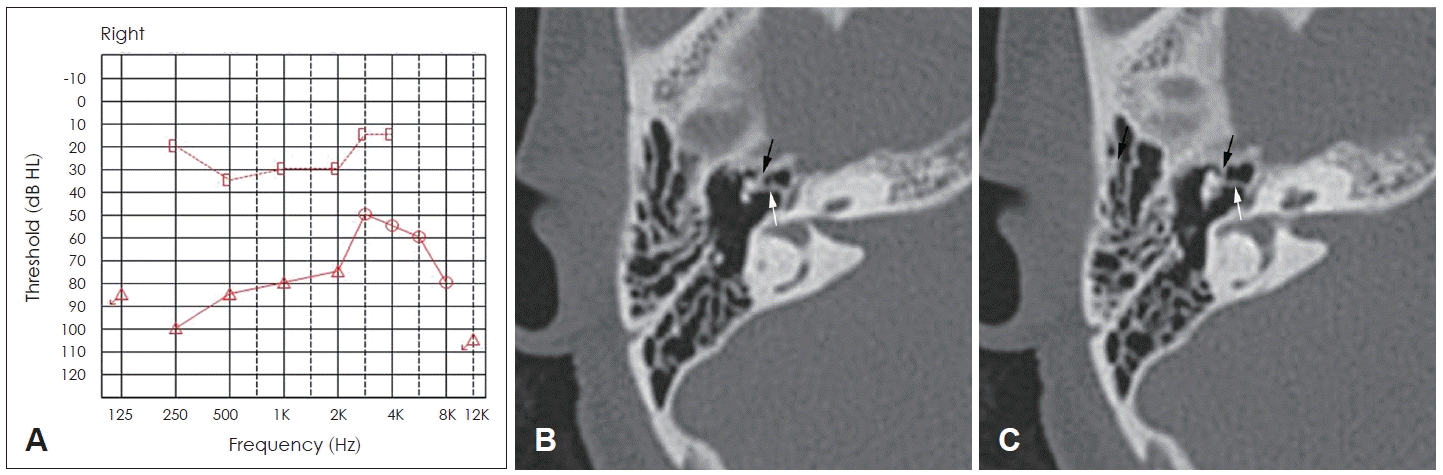

A 50-year-old woman presented with hearing loss on the right side since childhood. Physical examination revealed an intact tympanic membrane. Pure-tone audiometry of the right ear showed an air-bone gap of 45 dB on average from 0.5 to 3 kHz (Fig. 1A). Axial temporal bone computed tomography scan showed bony bridges between the malleus head and medial and anterior epitympanum (Fig. 1B and C). No otospongiotic foci were detected in the scans. Under general anesthesia, an endaural approach was used under microscopic view. A tympanomeatal flap was elevated, and the middle ear was exposed. Ossicular mobility was checked, and the malleus was fixed. After separating the incudostapedial joint, the mobility of the incus and stapes was rechecked. The stapes was also fixed. A limited atticotomy was performed with a curette and burr for better visualization of the epitympanum. The endoscope was then introduced, and the ossicular status in the epitympanum was examined using a 0 or 30 degree endoscope. A bony bridge was observed between the malleus head and the medial epitympanic wall, which made the malleus immobile. The endoscope was used to completely visualize this. The malleus was also fixed to the anterior epitympanic wall due to a similar bony bridge being present between the two structures (Fig. 2A and B). The fixed malleus head was freed from the surrounding epitympanic wall by fracturing the bony bridges using microinstruments (Fig. 2C and D) and removed using a malleus nipper (Fig. 2E and F). The tympanic membrane attachment to the malleus handle was separated approximately 1 mm caudal to the lateral process of the malleus. The incus was removed, and the stapes suprastructure was cut using crurotomy scissors. Under microscopic view, adequate length of the piston and inclination were estimated using a measuring rod and the 0.4 mm Fisch titanium stapes piston. The stapes footplate was fenestrated, and the piston was inserted into the stapes footplate opening. The piston loop was crimped to the malleus handle. The insertion site was sealed using harvested pieces of soft tissue and glue. Attic reconstruction was performed using harvested tragus perichondrium and cartilage. The tympanomeatal flap was restored to its original location. The postoperative course was uneventful, and the pure-tone audiogram at 6 months showed 12.5 dB of air-bone gap on average from 0.5 to 3 kHz, with a 32.5 dB closure of the preoperative air-bone gap (Fig. 3).

Preoperative pure-tone audiogram and temporal bone computed tomography imaging. The average air-bone gap at 0.5 kHz, 1 kHz, 2 kHz, and 3 kHz is 45 dB, indicating conductive hearing loss (A). Axial scan shows bony bridges between the malleus head and anterior (black arrow) and medial (white arrow) epitympanic walls (B and C).